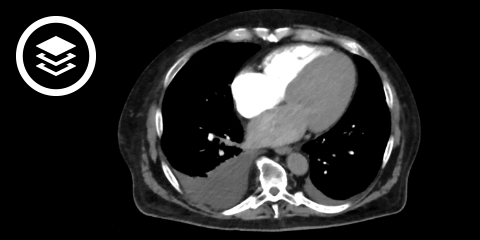

CT-Fallbeispiel

DICOM-Modelle können auf Mobilgeräten leider nicht angezeigt werden.